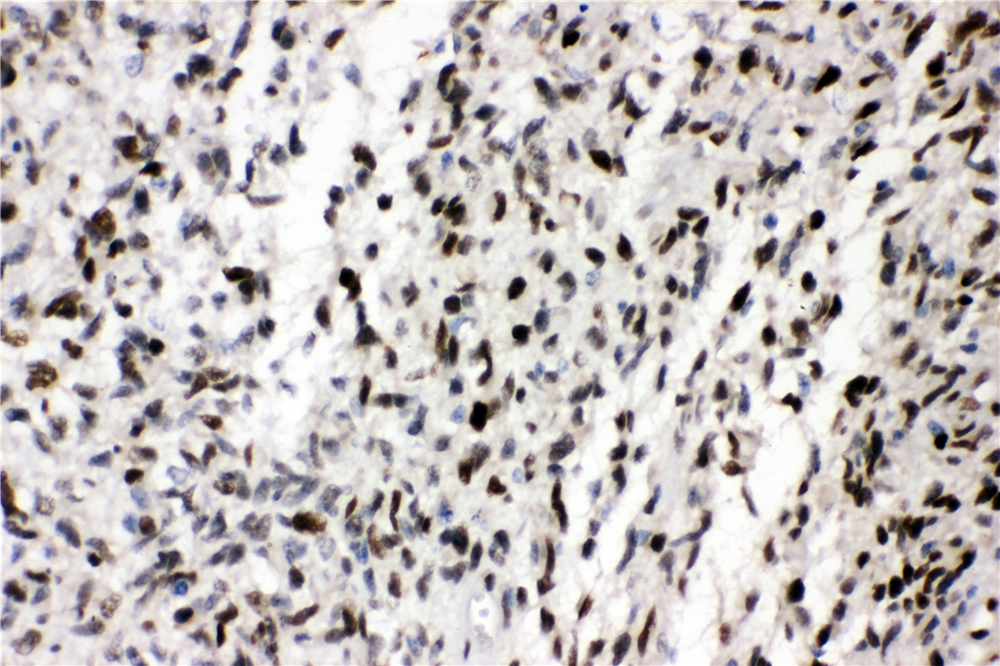

IHC analysis of ZEB1 using anti-ZEB1 antibody (A00548-2).

ZEB1 was detected in a paraffin-embedded section of human glioma tissue. Biotinylated goat anti-rabbit IgG was used as secondary antibody. The tissue section was incubated with rabbit anti-ZEB1 Antibody (A00548-2) at a dilution of 1:200 and developed using Strepavidin-Biotin-Complex (SABC) (Catalog # SA1022) with DAB (Catalog # AR1027) as the chromogen.